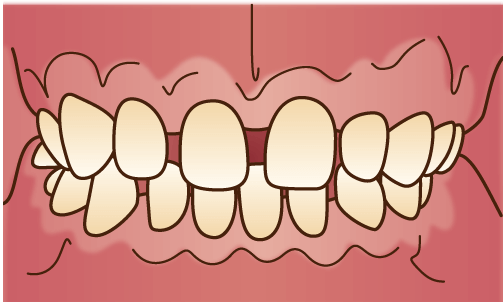

空隙歯列(くうげきしれつ)

隣同士の歯と歯の間に隙間がある状態。顎の大きさに対して歯が小さい場合や、歯の本数が少ない場合に起こりやすいです。隙間が目立つだけでなく、食べ物が挟まりやすくなります。

隣同士の歯と歯の間に隙間がある状態。顎の大きさに対して歯が小さい場合や、歯の本数が少ない場合に起こりやすいです。隙間が目立つだけでなく、食べ物が挟まりやすくなります。